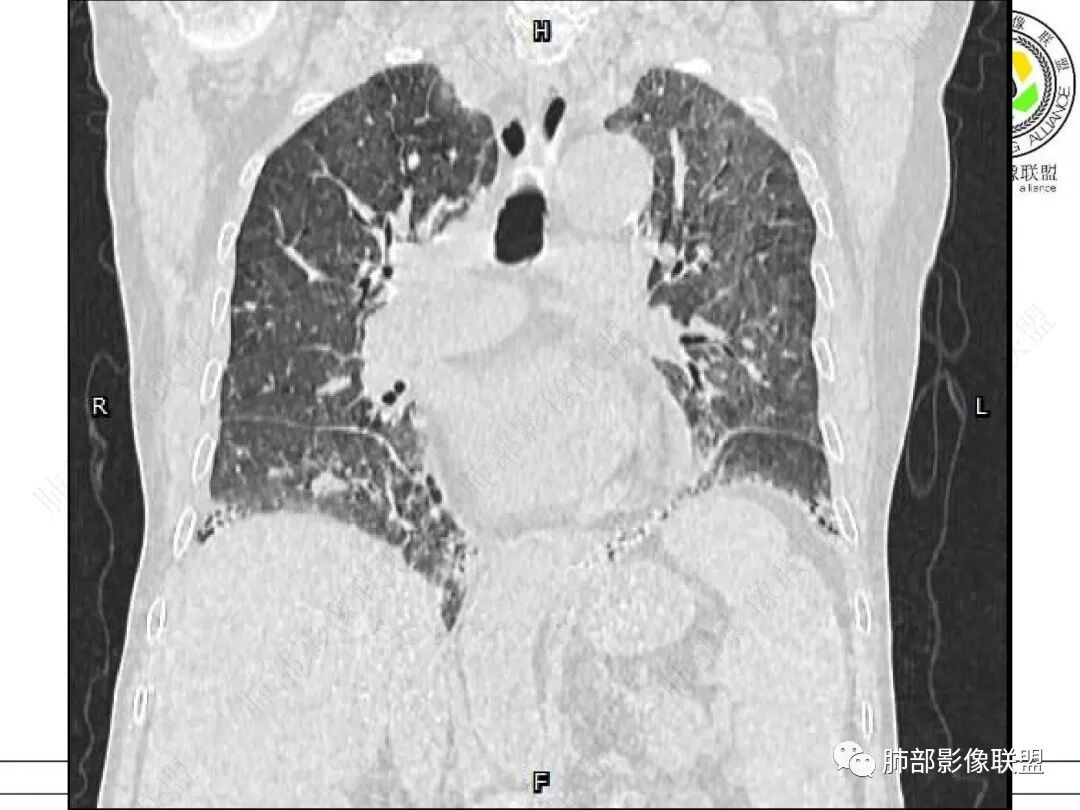

心脏大,胸腔积液,小叶间隔增厚,双肺磨玻璃影,考虑存在肺水肿,另双肺间质性炎性,类风关病史,考虑CTD-ILD,左肺上叶结核可能。

两肺叶后肋膈角区见多发蜂窝状结构破坏表现,双肺叶小叶间隔增厚,左肺上叶后段及舌段和右肺中叶胸膜炎性肉芽肿特点,双侧胸腔少量积液,有类风湿性关节炎治疗史,结缔组织相关性间质性肺病。

老年,外阴溃疡加发热,感染指标明显有异常,血气分析,过度呼吸及低氧血症,宿主因素,糖尿病和激素,基础疾病RA。影像,双下肺体积有缩小,有蜂窝?双肺磨玻璃,多发结节,双侧胸水。树芽不明确。是否有旧片,这个患者有UIP背景,是否感染或者UIP急性加重,或者基础上合并肺栓塞及肺水肿?长期激素,没有提供CD4细胞亚群,存在2种情况,1,风湿病没有压制住,肺考虑CTD相关性间质改变,压制过猛,结合感染指标,奴卡是有可能的。激素加糖尿病,结核也带排,激素加磨玻璃加G实验阳性,PCP也带排,临床信息太少,进一步排查

老年女性,有高血压糖尿病及类风湿性关节炎病史,发病前发烧。影像学两肺弥漫性磨玻璃影及斑片影,有渗出性病变亦有间质性改变,支气管血管束增粗,有牵拉扭曲有小气管扩张及间质增厚,两肺下叶胸膜下少许蜂蜜状影。两侧胸腔积液。考虑类风湿性关节炎肺内浸润?合并真菌感染?

老年女性,类风湿关节炎病史多年。发热。以两肺下叶为主弥漫磨玻璃及网格状透亮影,透亮度减低,局部小蜂窝状改变;两肺胸膜下散在几枚实性病灶;双侧胸腔积液。考虑RA-ILDNSIP

两下肺多发蜂窝状表现,双肺小叶间隔增厚,双肺磨玻璃影及部分炎性肉芽肿表现,双侧胸腔积液,有类风湿性关节炎治疗史,结缔组织相关性间质性肺病。患者C反应蛋白和降钙素原都高,是否合并细菌感染

女,71,外阴疼痛2周,发热1周。类风关、高血压、高血糖、卵巢囊肿、肠粘连、胆囊结石等病史及相关药物治疗史。胸部CT:两肺弥漫磨玻璃,血管束增粗,两下肺后肋膈角多发蜂窝,对称分布,双侧胸腔少量积液,纵隔窗心脏大血管影明显增宽。考虑混合性病变,CTD-ILD,并肺水肿?并PJP?。

双肺小叶间隔增厚+磨玻璃密度,双肺下叶胸膜下蜂窝,符合肺间质改变表现。双侧胸腔积液。患者类风湿,目前有外阴多发溃疡,血管炎-白塞氏病可能。实验室检查,C反高,和G实验阳性,考虑CTD-ILD合并感染,

老年女性,外阴溃疡伴发热,有类风、糖尿病病史,血象及炎症指标高,G试验升高;影像:磨玻璃密度(中央分布为主)胸膜下蜂窝状改变心影增大、两侧胸腔少量积液;小叶间隔增厚,结节;考虑:1.中央分布为主的GGO需考虑:肺水肿、出血、PJP、肺泡蛋白沉着症;2.胸膜下间质性改变蜂窝肺,需考虑UIP、CTD-ILD,综合:两元论:CTD-ILD奴卡,或肺水肿

双肺下叶多发蜂窝影,双肺小叶间隔增厚,双肺磨玻璃影,双侧胸腔积液,有类风湿性关节炎,考虑结缔组织相关性间质性肺病,合并感染

①影像表现复杂:较弥漫间质性改变,对称磨玻璃密度为主,小叶间隔增厚,有一定重力分布趋势,未见明显纤维化,气囊及蜂窝位于肺边缘,未见典型“月弓征”。心脏影增大,双侧胸腔积液。

这即可见于间质性肺病,也可见于真菌感染(如PJP)、病毒感染,类风湿,以及肺水肿等等。

一般而言,如存在磨玻璃密度影浑浊,有重力分布趋势,肺表面蜂窝影,胸腔积液等等,并不常见于单纯PJP,除非其他因素叠加。

患者存在肺水肿应当是合理的解释。其他旁证还有,心脏影增大,肾小球滤过率降低,双侧胸腔积液等等……

上肺斑片影、结节影,夹杂纤维条索影,边界清楚,新旧不等,胸膜牵拉明显等等,符合较典型继发性肺结核表现,但它却未必是此次就医主要责任病原体!